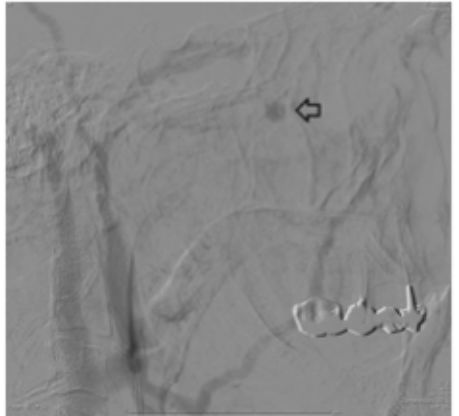

一位66岁的男性患者因右侧鼻出血入院,评估情况后暂时予以鼻腔填塞。2天后拔除鼻塞并行鼻内镜检查,可见右侧蝶腭孔区域有持续性出血,遂双极电凝该侧蝶腭动脉,再次填塞鼻腔,效果良好。15天后患者再次因严重的右侧鼻出血入院,此时已有贫血,遂行血管造影,提示出血来自于右侧上颌动脉的一终末分支。尽管术中栓塞了上颌动脉的远端,但术后症状并未得到控制。因此患者接受了二次鼻内镜手术:术中开放蝶窦、筛窦,扩大右侧上颌窦窦口,去除部分腭骨眶突及上颌窦后壁内份骨质充分暴露翼腭窝,仔细探查蝶腭段上颌动脉及其分支,最终磨除腭骨蝶突后发现出血来自于咽动脉,予电凝离断。术后出血控制,随诊3年无复发。

局麻下经股动脉穿刺右侧颈外动脉造影,可见蝶骨体底水平的黏膜有迟发性出血(箭头所示),考虑责任血管为上颌动脉的终末分支。